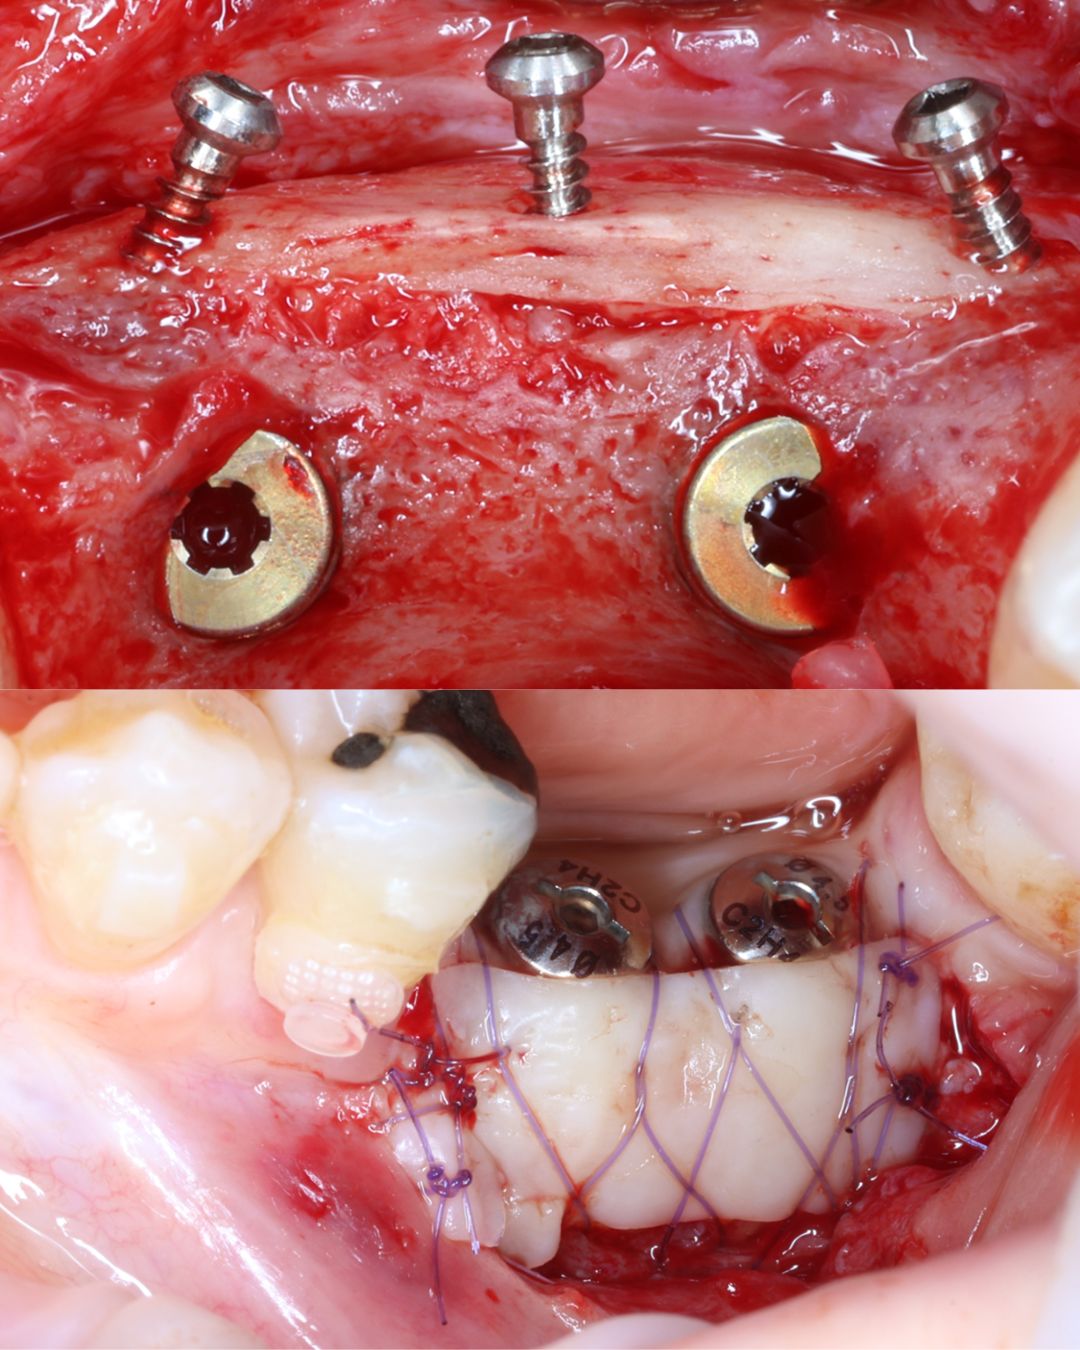

High Quality Surgical Recordings

Study high-quality surgical recordings that capture procedures step-by-step, allowing you to observe critical decision-making, tissue handling, and anatomical management in real clinical scenarios.

- GBR Using Periosteal Mattress Sutures (Hands On)

- GBR Using Tacks and Screw Fixation (Hands On)

- ARF + FGG (Hands On)

- Kanzanjian Vestibuloplasty (Hands On)